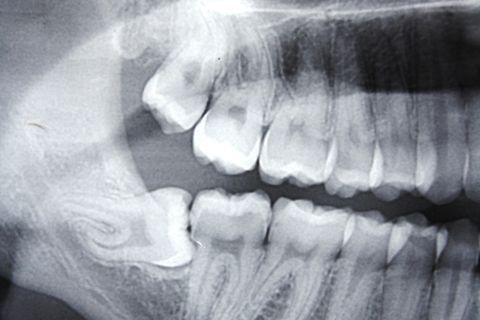

Paciente AB, sexo feminino, 19 anos, com indicação para exodontia dos elementos 18 e 48 incluso e mesio-incliniado.